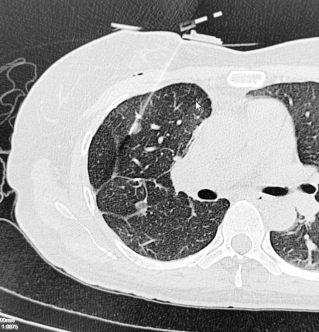

由于既往右肺手术切除范围大,且术后胸腔粘连,再次手术创伤大,患者多方辗转后被推荐前往华西医院就诊治疗。2024年7月31日,患者为寻求进一步治疗来到我院胸外科廖虎副教授门诊就诊。胸部CT检查显示,患者右肺中叶可见一新发混合密度磨玻璃结节,大小约为0.8cm×0.6cm,边界较清晰;左肺下叶基底段小结节大小约0.3cm×0.2 cm。

围绕患者病情,刘伦旭教授、蒲强教授、廖虎副教授团队经过讨论,总结为:第一,患者肺癌术后,双肺多发小结节,其中右肺中叶新发混合密度结节随访过程中逐渐增大,有干预指征。患者三年前已行手术切除右肺多处组织,为避免再次手术影响呼吸功能和生活质量,可考虑选择经皮穿刺的肺结节射频消融治疗。第二,该结节大小为0.8×0.6cm,体积较小,既往手术的吻合钉可能干扰穿刺路径,常规方法难度大、风险高,可选择可精准定位导航的机器人进行辅助穿刺。在与患者及家属充分沟通后,团队决定采用穿刺导航机器人辅助、联合CT完成肺结节射频消融术。

随后,团队进行了扎实的术前准备,包括穿刺方案、消融方案,以及术中可能遇到的并发症及应对措施,术后并发症的预防和处置方案等。2024年8月11日,手术进行,刘伦旭教授、蒲强教授进行指导,廖虎副教授主刀。术中,首先将CT扫描实时数据导入穿刺导航机器人,并在机器人上规划预设好穿刺路径,通过呼吸门控技术过滤掉患者自主呼吸的影响,然后在机械臂红外激光的引导下进行穿刺,穿刺成功后行射频消融治疗。